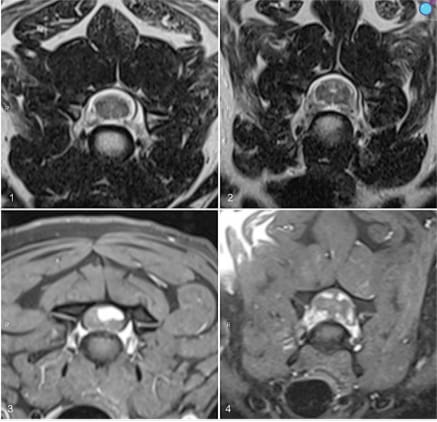

Magnetic resonance imaging of the cervical spinal cord of a dog with multiple spinal nerve sheath tumors. Figures 1, 2. Transverse T2-weighted images centered on the cervical vertebral column at the C7-T1 (Fig. 1) and C6-C7 (Fig. 2) intervertebral disc spaces showing nerve root thickening, highlighted by T2-weighted hyperintensity, with variable degrees of asymmetry in the thickenings. Figures 3, 4. Transverse T1-weighted fat-saturated post-contrast images centered on the cervical vertebral column at the C3-C4 (Fig. 3) and C6-C7 (Fig. 4) intervertebral disc spaces. Multiple intradural nodular lesions have uniform contrast enhancement with well-defined borders, some extending into the spinal cord parenchyma.